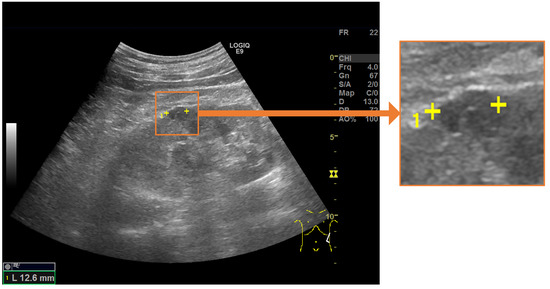

- To predict the landmarks for multiple renal cysts within one image, we developed a system in which all renal cysts in the image were detected prior to saliency map regression. Then, we performed saliency map regression to predict the positions of two salient landmarks for each detected renal cyst.

2.1. Automated System for Assigning Salient Landmarks

2.3. Saliency Map Representing the Location of Salient Landmarks

2.4. Salient Landmark Position Prediction Model